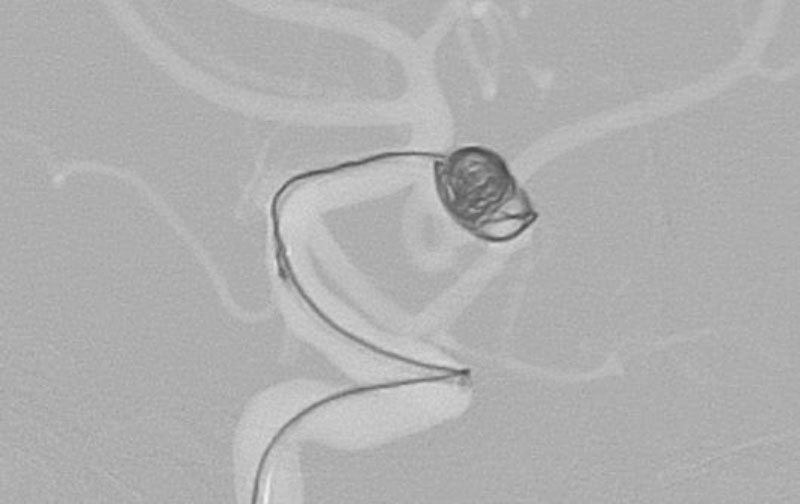

No.1631 手術前

No.1631 手術中

No.1631 手術後